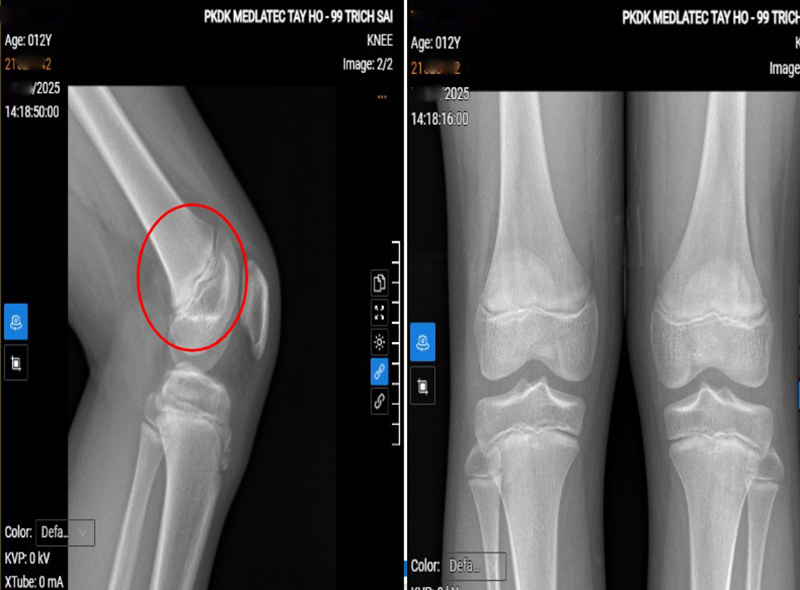

Để chẩn đoán bệnh, bác sĩ chỉ định làm một số cận lâm sàng cần thiết tại khớp gối trái. Kết quả: siêu âm khớp thấy phù nề nhẹ tại điểm bám gân bánh chè; X-quang ghi nhận hình ảnh theo dõi hoại tử vô khuẩn lồi củ xương chày; MRI phát hiện phù nhẹ dây chằng chéo trước, phù xương và mô mỡ quanh lồi củ chày - gợi ý bệnh cảnh viêm lồi củ trước xương chày.

Hình ảnh chụp X-quang khớp gối trái của bệnh nhân